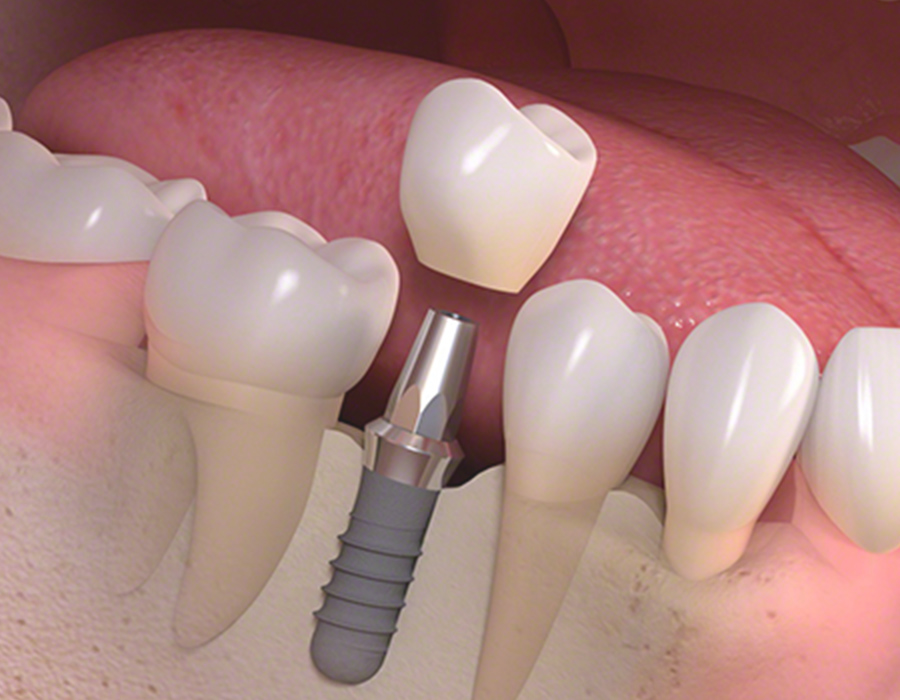

診療案内 medical information ホーム 診療案内 当院の治療のご案内 虫歯治療なるべく虫歯以外の部分を削らないようにし、患者様にも確認してもらいながら治療を進めます。もっと見る 予防歯科 (PMTC) 虫歯の早期発見のためにも当院は定期的な予防歯科をおすすめしております。もっと見る 小児歯科小児歯科は、成長発達期にある子どもの歯および顎や口を管理し、発育を助けるための医療です。もっと見る セレック即日で治療を行います。天然歯に近い美しいセラミックで、きれいに治療します。もっと見る 審美歯科虫歯治療をはじめ、気になっている箇所を美しく治療します。もっと見る ホワイトニング歯を削らずにスピーディーに歯を白くします。治療回数は3回となっております。もっと見る 歯周病治療歯茎が下がってきたり、口臭が気になる方に検査を受けていただき、最適な治療を行います。もっと見る インプラントインプラントをいれたその日からご飯が食べられます。入れ歯が合わない方もご相談ください。もっと見る デンチャー(入れ歯)60年の伝統に裏打ちされた治療を行います。もっと見る 訪問診療ご自宅や、施設まで診療に伺います。もっと見る 根管治療(歯の根の治療)再発がなるべく起こらない治療を目指しています。もっと見る かぶせ物やつめものの再発を少なくするために大切な身体の一部である歯を、可能な限り残す治療に取り組みます。もっと見る 親知らず抜歯大学病院に勤務しているDrによる親知らず抜歯を行っております。もっと見る 歯の移植歯がなくなった場合、インプラント、ブリッジ、入れ歯以外に、第4の選択肢として、歯の再植というものがあるのはご存じですか?もっと見る 有病者歯科ご病気のある方、基礎疾患、既往のある方の歯科治療。もっと見る 子供や大人の歯と口のケガ(外傷)当院では、近在教育機関の校医を行っており、長年歯や口のケガをした方の対応をしております。もっと見る マタニティ歯科これから妊娠をお考えや、妊娠中の方で、お口の中のトラブルひいては胎児への影響を少なくするために努めていきます。もっと見る セラミック、かぶせもの、詰め物の治療機能性にも審美性にもこだわる、調和のとれた審美治療を行います。もっと見る 矯正治療 歯並び 不正咬合部分矯正、ワイヤー矯正、マウスピース矯正、マウスピース矯正とワイヤー矯正を組み合わせて行うコンビネーション矯正治療が可能です。もっと見る 鎮静による治療法、当院が行っている痛みの少ない治療への取り組み、歯科集中治療のご提案無痛治療とまではいかないまでも極力痛みを少なくした状態で歯科治療を目指す方法として鎮静法があります。もっと見る 顎関節治療、歯ぎしり、噛みしめの治療顎関節症の原因は、様々な因子が関係しているといわれております。当院は大学病院口腔外科にて幅広く研鑽をつんだ副院長が、顎関節治療を行っております。もっと見る